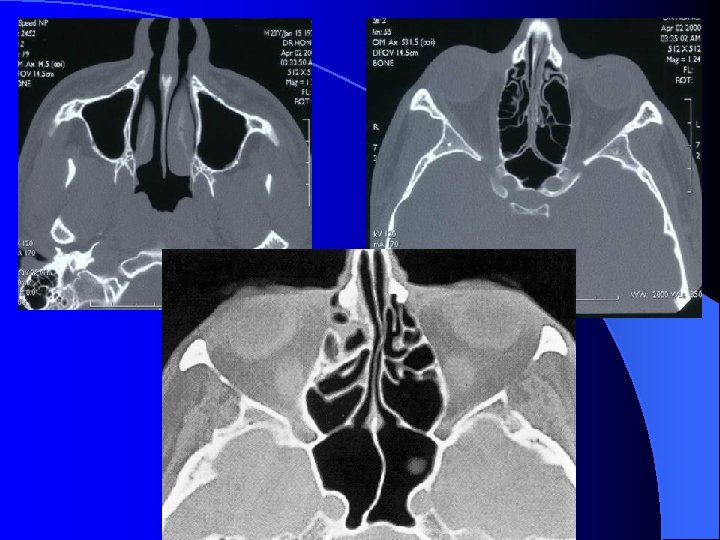

IMAGERIE DES CAVITES RHINO SINUSIENNES TDM FACIALE Coupes coronales, frontales et sagittales

MALADIES INFECTIEUSES RHINO SINUSIENNES SINUSITE MAXILLAIRE CHRONIQUE IMAGERIE Radiographies standard Blondeau (nez-menton-plaque): CE, Niveaux hydro-aérique Panoramique dentaire: Etat bucco-dentaire, signes unilatéraux TDM crânio-faciale IRM crânio-faciale

MALADIES INFECTIEUSES RHINO SINUSIENNES ETHMOIDITE AIGUË IMAGERIE • Radiographie standard • Echo doppler couleur (opérateur dépendant) • TDM sans et avec injection siège, stade collecté, analyse orbitaire fine